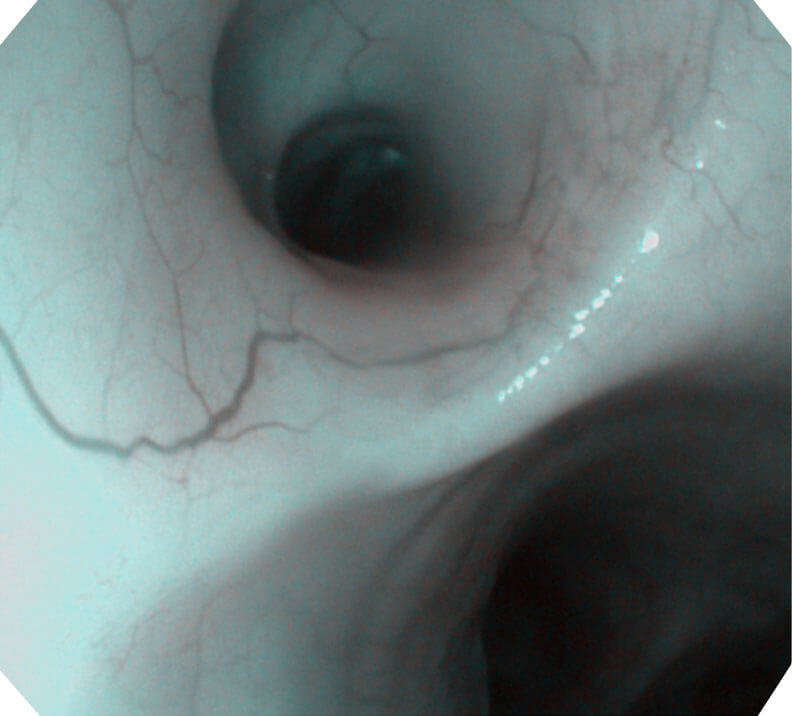

光电复合染色成像技术

(Versatile Intelligent Staining Technology, VIST)

光电复合染色成像技术(VIST)是一种光学滤波和数字滤波相结合的染色成像技术,摒弃了滤光转轮而直接采用光谱组合的方案,加入了血红蛋白吸收高峰与次高峰的蓝紫光和绿光光谱,更有利于黏膜血管吸收,突显浅表层血管和中层血管的对比度,因而具备更高的图像对比度,有助于观察微细结构变化及病灶边界的观察。